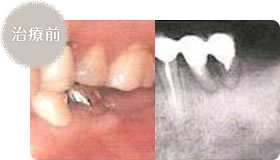

- 奥歯2本をなくしており、ブリッジでは対応できません

- 自分の歯と同じように修復ができました

奥歯をなくし、部分入れ歯(義歯)でしか対応できなくなってしまった場合、インプラントにより他の歯に負担をかけることなく自然の歯に近い噛み心地や審美性が得られるようになります。

多くの歯がなくなっていますので、インプラント治療以外では部分入れ歯でしか対応できない状況です。

インプラント埋入予定部位です。

インプラントを埋入しました

手術後、歯ぐきが治癒して二次手術前です。

人工歯をかぶせて、かめるようになりました。